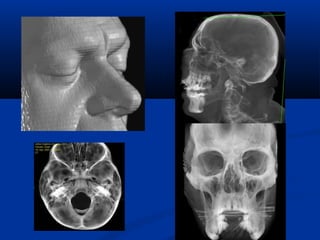

U maùu vuønghaømU maùu vuøng haøm (T)/(T)/ Daõn tónh maïchDaõn tónh maïch caûnh ngoaøi (T)caûnh ngoaøi (T)